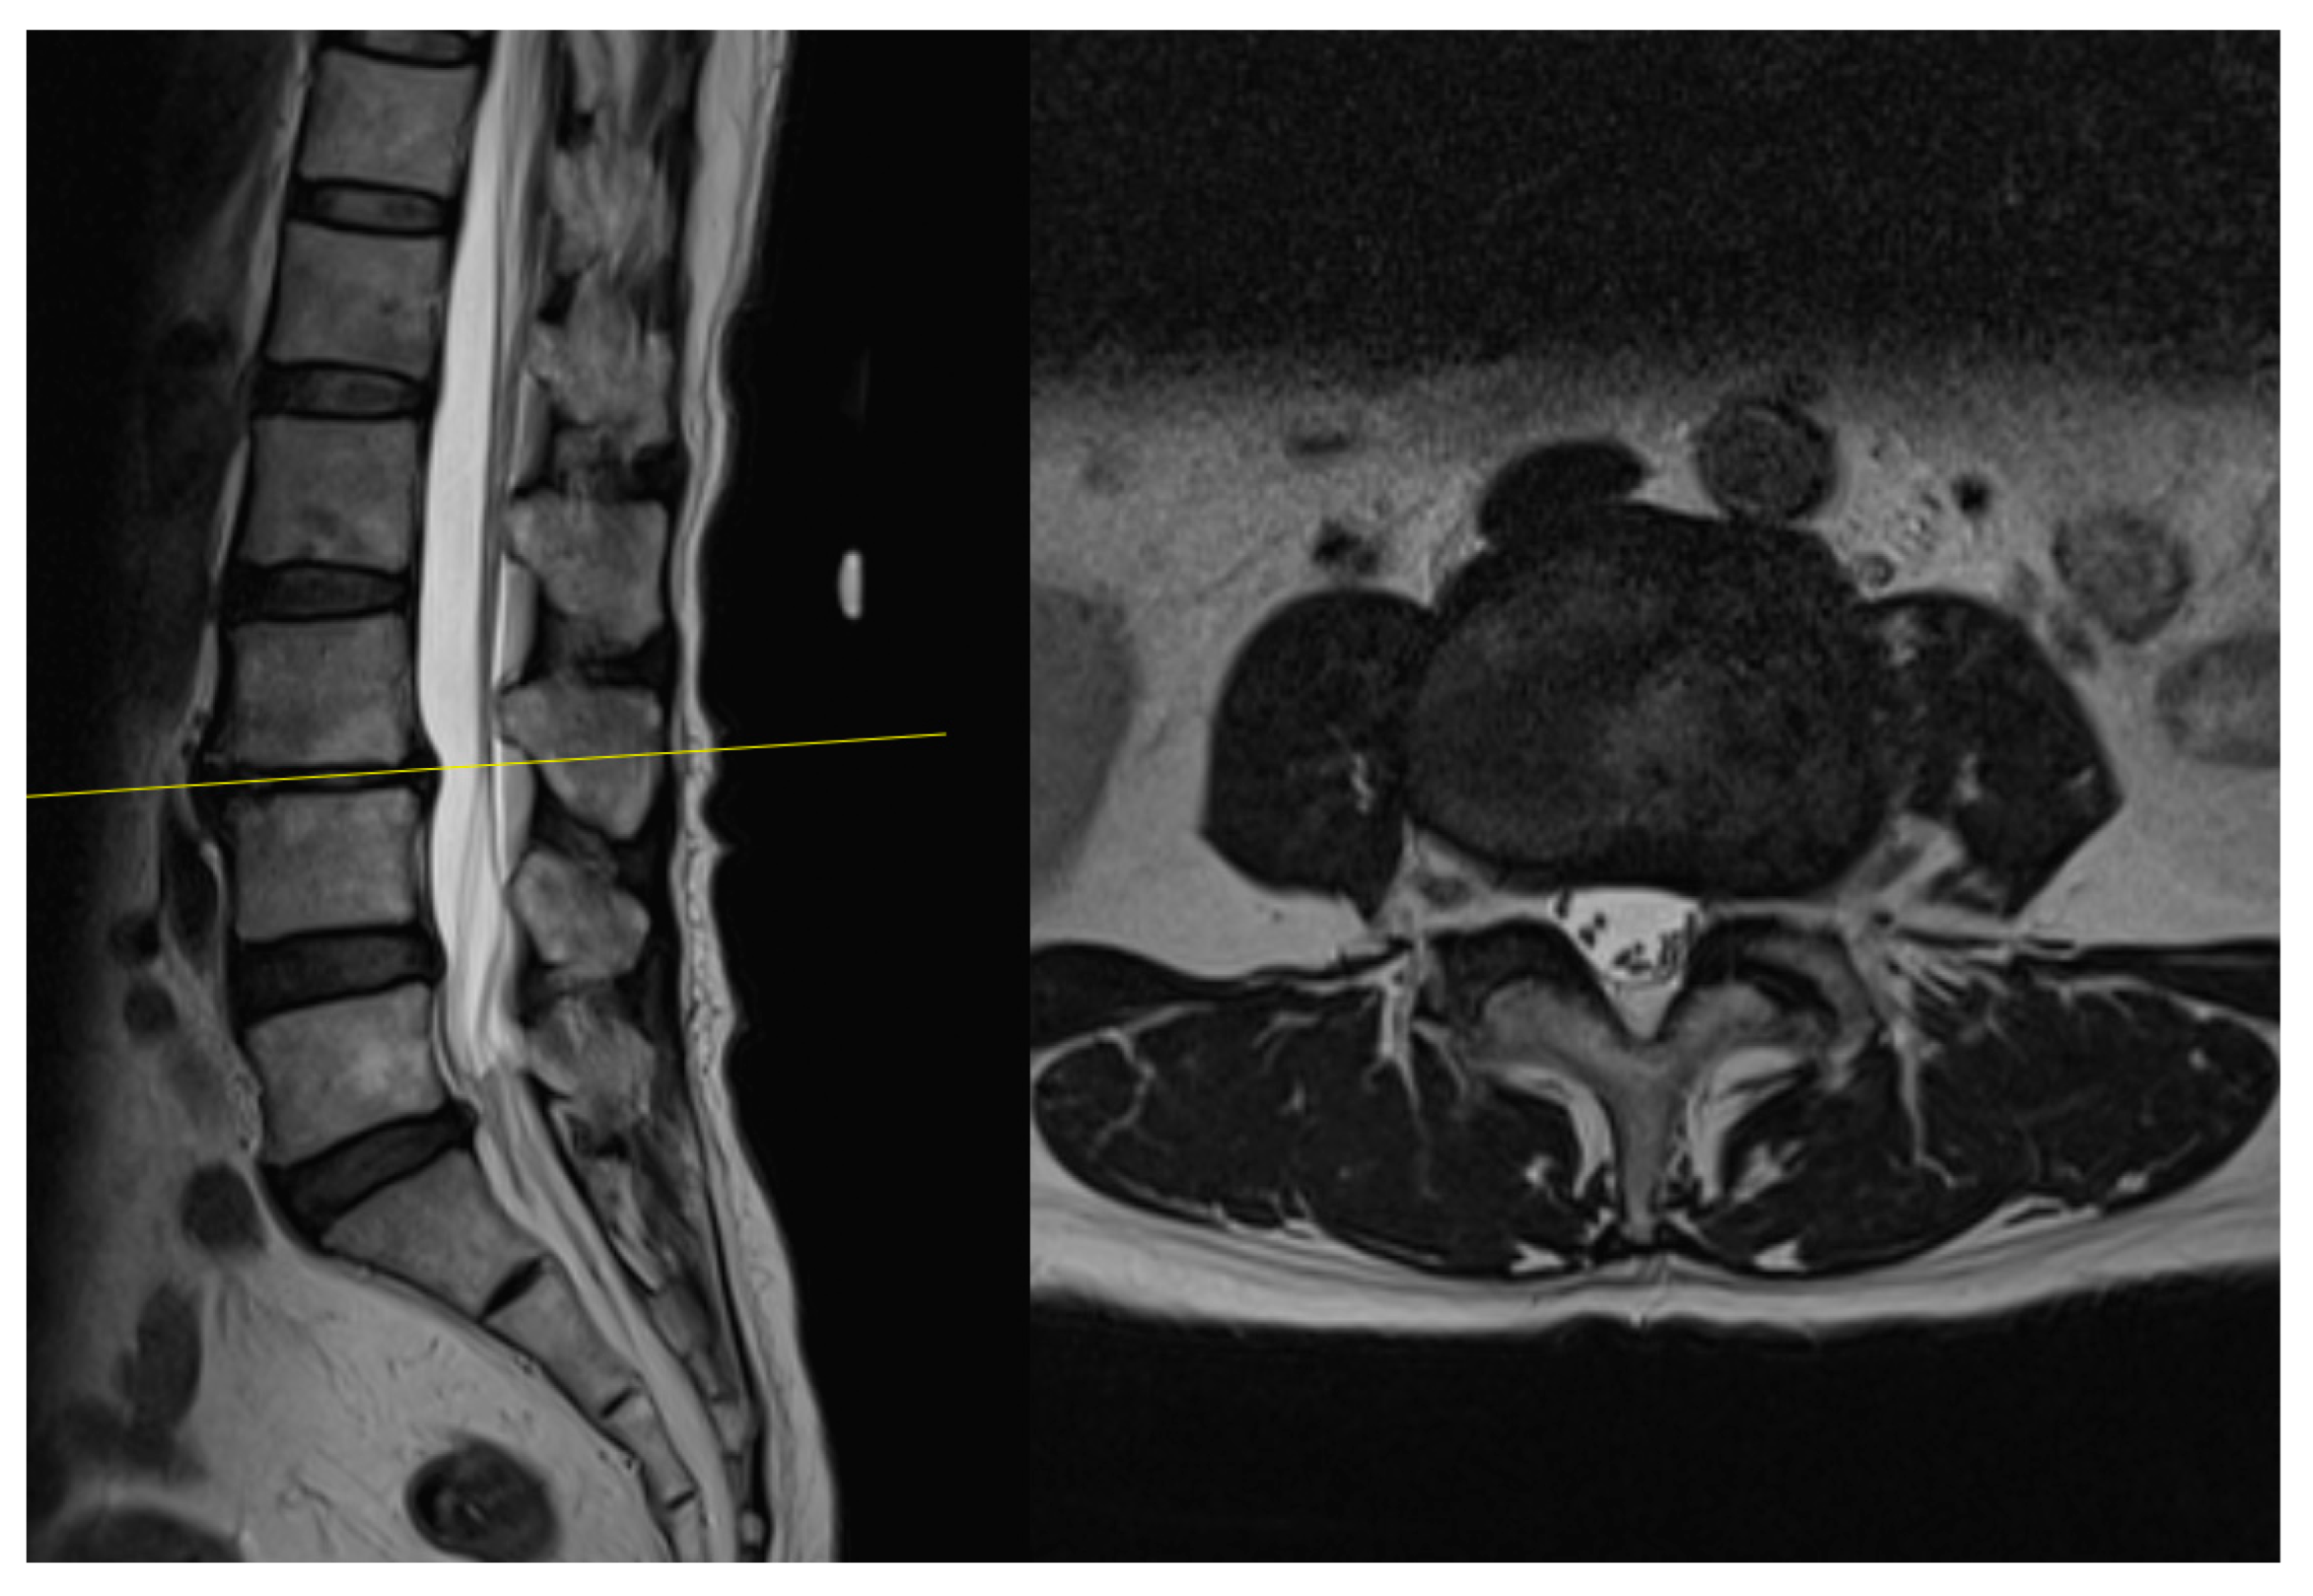

4.1. Case 1: Madam M

4.2. Case 2: Madam R

4.3. Case 3: Madam M